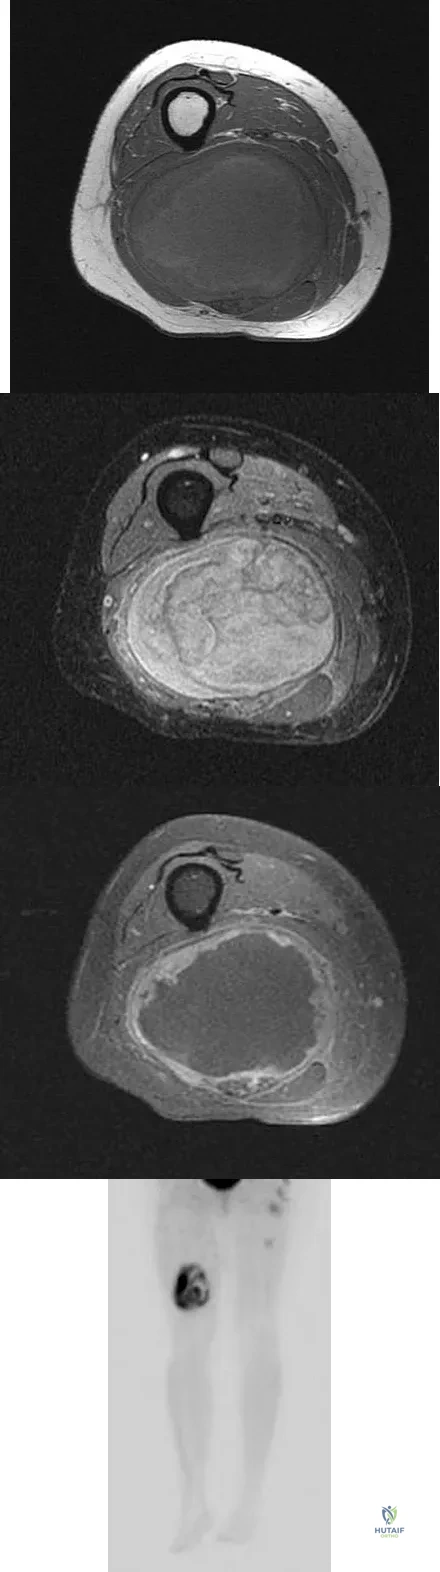

A 36-year-old woman with familial neurofibromatosis has an enlarging mass in the posterior thigh. The lesion has slowly increased in size and is now constantly painful. Pressure on the mass causes dysesthesias in the foot. Figures 44a through 44c show T1-weighted, STIR, and T1-weighted fat-saturated gadolinium scans, respectively. Figure 44d shows a PET scan. What does this lesion most likely represent?

Explanation

The images reveal a large mass in the posterior thigh arising from the sciatic nerve. The lesion is edematous, and the gadolinium image reveals rim enhancement, suggesting necrosis, given that the STIR image is not uniformly bright as would be seen in a cystic lesion. The PET scan has increased uptake, in this case a standard unit value (SUV) of greater than 2.0. These findings are all very suggestive of a malignant process. The history of neurofibromatosis makes a malignant peripheral nerve sheath tumor, or neurofibrosarcoma, the most likely diagnosis. The term "peripheral nerve sheath tumor" has replaced neurolemmoma and schwannoma. Menendez LR (ed): Orthopaedic Knowledge Update: Musculoskeletal Tumors. Rosemont, IL, American Academy of Orthopaedic Surgeons, 2002, pp 225-230.